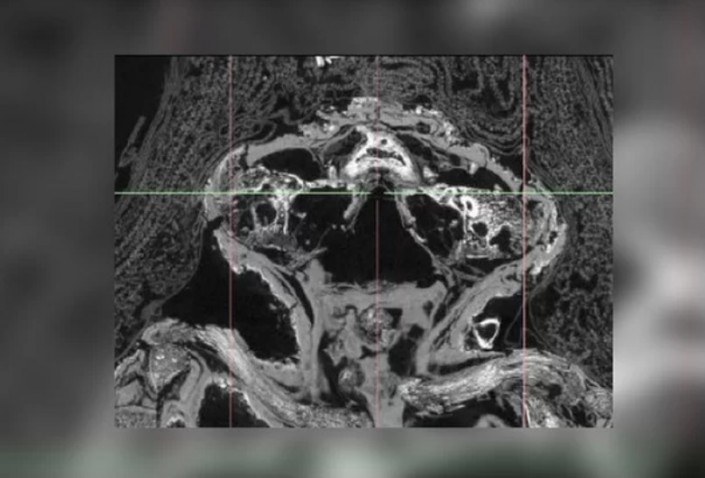

Открыв эту аномалию, работники музея связались с Нельсоном и его коллегами, специалистами в области компьютерной микротомографии. Ученые просветили мумию при помощи сканера и смогли увидеть даже самые мельчайшие ее детали, которые рассказали им о том, кто на самом деле был погребен под слоем позолоченного папируса и тканей.

Внутри ее "савана" команда Нельсона нашла тело недоношенного ребенка, умершего примерно на 26-28-й неделе после зачатия. Причина его смерти была очень простой - он страдал от анэнцефалии, полного отсутствия мозга. Сегодня подобные генетические дефекты поражают каждого десятитысячного младенца, подавляющее большинство которых гибнет еще до рождения.